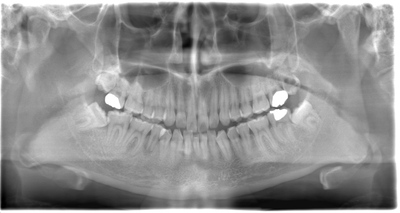

CASE 4

| 年齢・性別 | 30代・男性 |

| 主訴 | 左上親知らず抜きたい |

| 抜歯期間 | 15分 |

| 抜歯費用 | 約2,000円(保険内) 別途CT撮影で3,000円 |

| 抜歯内容 | 左上の親知らず抜歯 |

CASE 5

基本情報

| 年齢・性別 | 40代・女性 |

|---|---|

| 主訴 | 右上親知らず抜きたい |

| 抜歯期間 | 30分 |

| 抜歯費用 | 約2,500円(保険内) 別途CT撮影で3,000円 |

| 抜歯内容 | 右上の親知らず抜歯 |